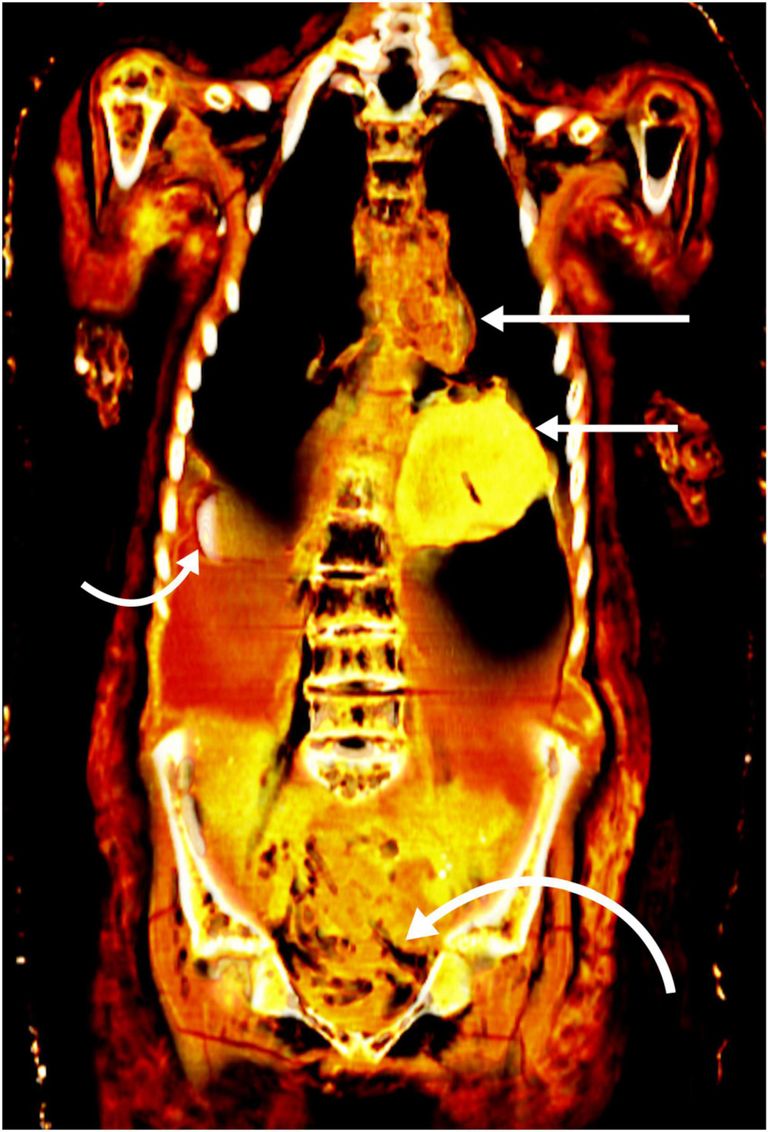

بدايةً جرت عملية الفحص في حديقة المتحف المصري بجهاز الأشعة المقطعية، وتمكنا من إزالة اللفائف بواسطة برامج عالية الجودة، حتى وجدنا المومياء ترتدي قناعًا مذهبًا، وصدرية مصنوعة من الكارتوناج، وصندل، وبين اللفائف عثرنا على 49 تميمة مرصوصة بشكل متناسق في 3 صفوف.

التمائم التي وجدناها مميزة وغير اعتيادية نظرًا لعددها الكبير، كما أن لها 21 شكلًا مختلفًا، و30 قطعة منها مصنوعة من الذهب، والبقية من بعض أنواع الأحجار، وتواجدت في تجويف الصدر والبطن وغيرها من الأماكن.

ما دلائل وجود هذه التمائم داخل المومياء؟

التمائم لها أهمية لدى المصري القديم، فهي تعيد الحياة للأجزاء المختلفة من الجسم، مثلًا يوجد اللسان الذهبي حتى يتمكن الصبي من التحدث في العالم الآخر، وتميمة جعران القلب الذهبية الموضوعة في تجويف الصدر، تمثل "القلب بحيث ينبض في العالم الآخر، ولدوره في وزن الأعمال ودخوله مملكة الجنة" بحسب اعتقاد القدماء.